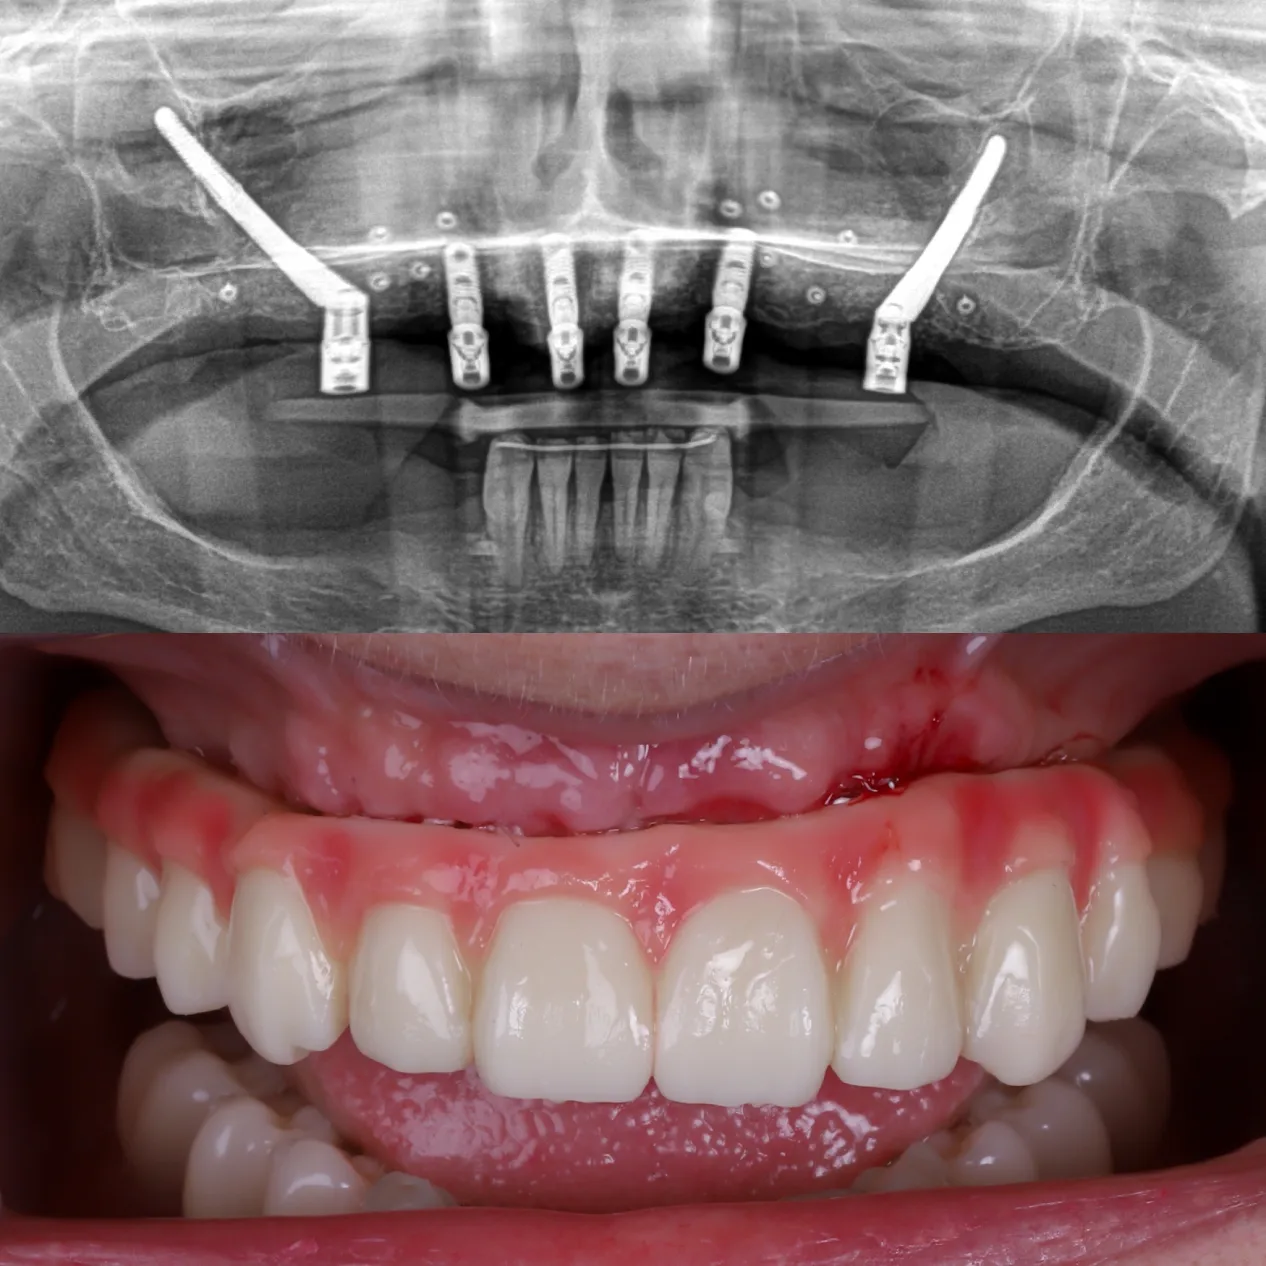

Los implantes cigomáticos son un tipo de implante dental especialmente diseñado para pacientes que no tienen suficiente hueso en el maxilar superior. A diferencia de un implante convencional, que se fija en el hueso del maxilar, el implante cigomático es más largo y se ancla en el hueso cigomático (el pómulo), una zona muy densa y estable que siempre mantiene suficiente estructura ósea, incluso cuando el maxilar está muy reabsorbido.

El número de implantes cigomáticos necesarios suele variar entre 1 y 4 por arcada y depende principalmente de la calidad del hueso maxilar y la calidad del hueso cigomático (pómulo). Cuando el hueso del maxilar no es suficiente, utilizamos el hueso cigomático (el pómulo) como punto de anclaje.

Sin embargo, cuando no existe buen hueso maxilar en ninguna zona, o incluso cuando el punto de apoyo en el pómulo no ofrece la estabilidad ideal, pueden necesitarse hasta 4 implantes cigomáticos para conseguir una fijación segura y permitir una rehabilitación fija inmediata.

Por eso es fundamental realizar un estudio personalizado con TAC 3D, que permite definir la combinación más segura, estable y adecuada para cada paciente.

Antes y después